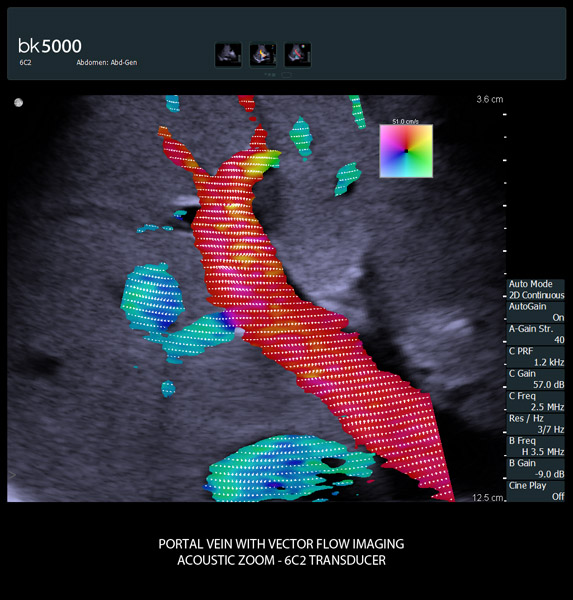

Addressing Challenges with Advanced Technologies

From the simplest diagnostic imaging to the most critical interventional procedures, every clinical situation has its own set of unique challenges. The bk5000 offers a full suite of innovative technologies and advanced controls and adjustments to help you achieve the best possible image quality, across many applications.